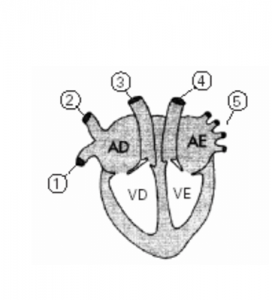

A respeito do desenho acima, que representa o coração de um mamífero, é INCORRETO afirmar que:

a) 3 é artéria pulmonar que leva o sangue do coração para o pulmão.

b) 1 é a veia cava inferior que traz o sangue do corpo para o coração.

c) 2 é artéria cava superior que leva o sangue do coração para o corpo.

d) 4 é artéria aorta que leva o sangue do coração para o corpo.

e) 5 são veias pulmonares que trazem o sangue dos pulmões para o coração.

Alternativa “c”. O vaso 2 é a veia cava superior, que traz sangue venoso das regiões superiores do corpo, não sendo, portanto, uma artéria.